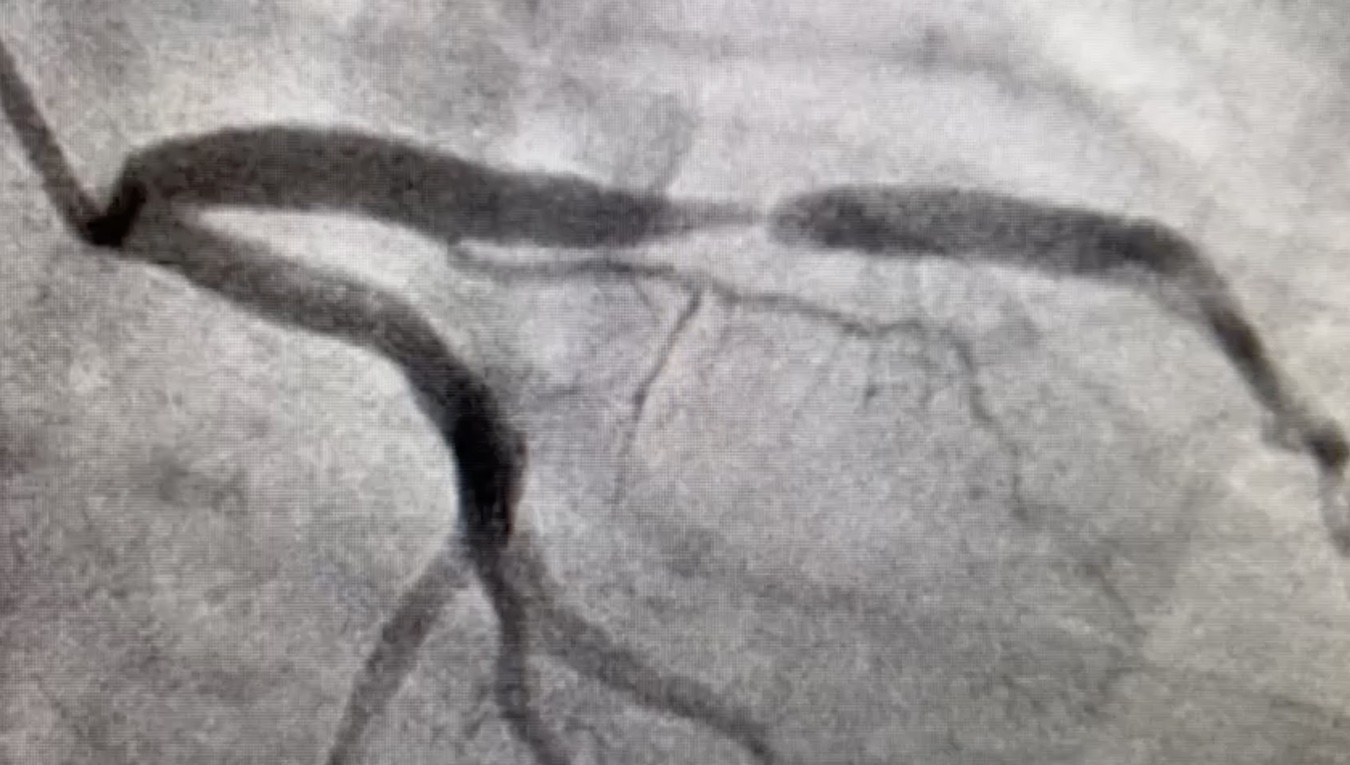

In the figures below are representative images from contrast CTs of two 63 year old asymptomatic female patients. Whereas the second has zero CAC, she had the more clinically severe coronary artery disease. The top figure shows heavy coronary artery calcification of the left anterior descending artery (LAD) that has developed without significant stenosis; the lower figure shows a critical stenosis as a result of a non calcified plaque that has nearly occluded the LAD. In this case there zero coronary calcium in any vessel. Life threatening disease was confirmed in the zero CAC case by invasive angiography a week later (where the critical narrowing was immediately treated with a stent).

An image of the invasive angiogram of case 2, taken a week later, confirming the CT findings. There is a severe narrowing (stenosis) affecting the left anterior coronary artery (LAD).

These images illustrate that although a raised CAC for age is associated with higher future coronary event rates, the absence of CAC does not exclude important coronary heart disease.